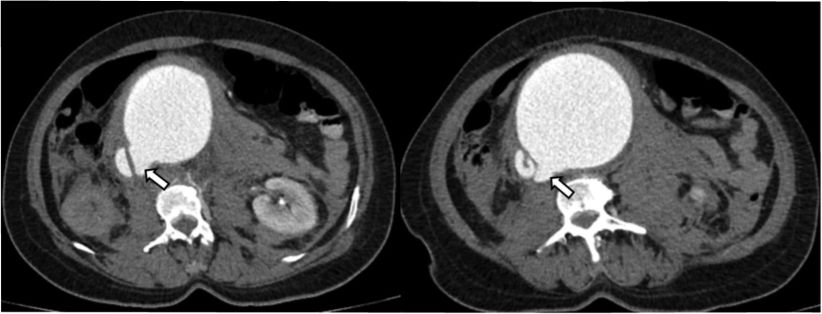

Paciente de 59 años de edad con cuadro clínico de 4 días de evolución consistente en dolor lumbar irradiado a abdomen. Es remitida para valoración, sin antecedentes personales o familiares de importancia. En el examen físico, el paciente está en condiciones generales regulares, taquicárdica, con masa palpable y pulsátil a la exploración abdominal. Se procedió a la realización de angioTC de abdomen. En la fase arterial se observó dilatación aneurismática de la aorta abdominal infrarrenal con un alcance de diámetro de hasta 94 mm con comunicación de la luz entre la aorta abdominal y la vena cava inferior sugestivo de fístula aortocava (Figura 1).

Figura 1 Angiotac de abdomen cortes axial y coronal. Opacificación de estructura venosa (VCI) durante la fase arterial del estudio con comunicación de la luz de la aorta abdominal y la vena cava inferior (flecha blanca) asociado a cambios inflamatorios periaórticos y hematoma (asterisco).